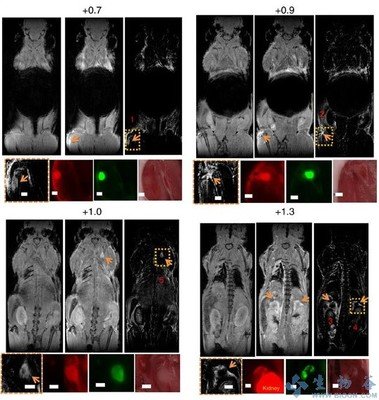

半导体苝酰亚胺纳米颗粒的尺寸大小对淋巴结定位及癌症成像的影响